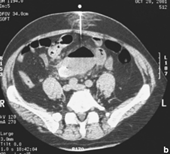

La TC mostrará tanto la aerobilia como el

cálculo ubicado en el intestino delgado y la dilatación proximal de éste.